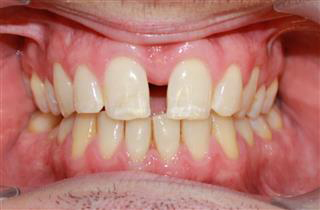

MSE treatment targets patients who are experiencing dental crowding, crossbites or breathing difficulties due to an underdeveloped maxillary arch. The procedure utilizes a specially designed device that is placed in the roof of the mouth. This device gently expands the maxillary bone over time, which is essential for promoting proper alignment and function of the jaw and teeth.

- Enhances facial aesthetics and symmetry.

- Corrects crossbites and improves overall dental alignment.